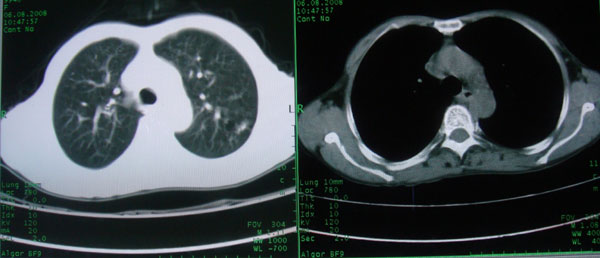

慢性支气管炎伴支气管扩张\\感染

慢性支气管病变并肺部感染。

支持慢性支气管病变并肺部感染。

肺间质性改变 支气管扩张合并感染

慢性支气管炎伴全小型肺气肿、支气管扩张、感染、间质纤维化。